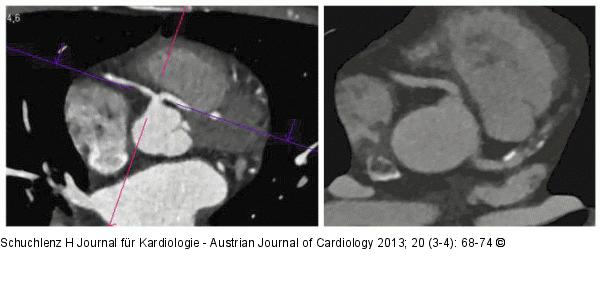

Abbildung 4a-b: Herz-CT (a): LAD entspringt aus dem rechten Koronarsinus und verläuft zwischen Pumonalis und Aorta (maligner Verlauf); (b): Normaler Ursprung von LAD und RCA (hochgradig stenosierender vorwiegend „weicher“ Plaque in der LAD). |

(a): LAD entspringt aus dem rechten Koronarsinus und verläuft zwischen Pumonalis und Aorta (maligner Verlauf); (b): Normaler Ursprung von LAD und RCA (hochgradig stenosierender vorwiegend „weicher“ Plaque in der LAD). |